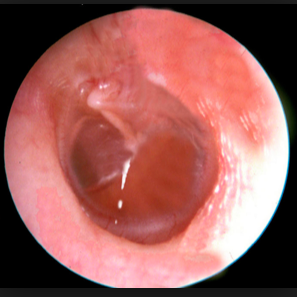

1. Otoscopia

1. MT perforada, otorrea

2. TAC